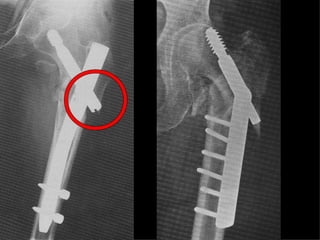

3  INSUCCESSI

F. 72a

F. 77a

F. 84a

CONCLUSIONI Perché non mettere un chiodo?  Senz’altro se il muro  laterale è fratturato  così come il punto di introduzione della  vite cefalica,perché la tecnica è più semplice

… ma  se il muro laterale è integro , la sintesi con la placca di Gotfried è  migliore e se  applicata con la  necessaria perizia tecnica garantisce  ottimi risultati.

2 Insuccessi